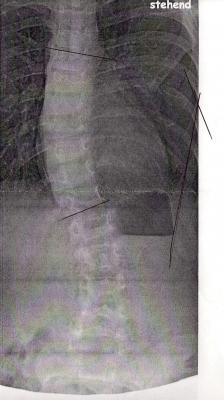

herr rahmouni sagte, er wollte die hws sehen - am besten bis zum beckenkamm - aber ich finde, man erkennt so gut wie nix im unteren bereich :(

toll - jetzt hab ich mir die "alten" und die "neuen" bilder mal angesehen ... meiner meinung nach, hat sich die skoliose ordentlich verschlechtert - findet ihr das im direkten vergleich auch? *bildanhäng*

ob das Röntgen ausreichend ist, kann ich dir leider nicht sagen. Ich glaube, das Becken auf dem Bild ist wichtig, um zu sehen, ob ein Schiefstand besteht und ob das Becken verdreht ist. Bei den Bildern von Dr. Hoffmann sieht man auch noch die Körperkonturen mit, also z.B. die herausstehende Hüfte ist da mit ersichtlich. Was bei beiden Bildern aber fehlt, ist das Gitter im Hintergrund. Daran sieht man z.B. besser, ob die Wirbelsäule im Lot steht.

meiner meinung nach, hat sich die skoliose ordentlich verschlechtert - findet ihr das im direkten vergleich auch?

Wieso wurde das neue Bild denn nicht ausgemessen? Ich glaube auch, dass es sich oben etwas verschlechtert hat, in der LWS siehts dafür etwas besser aus. Könnte also sein, dass sie einfach etwas anders stand. Aber ab Morgen gehts dann ja eh aufwärts, d.h. erstmal wirds wohl schwierig mit der Eingewöhnung, aber die Sorge der ständigen Verschlechterung ist erstmal weg :)